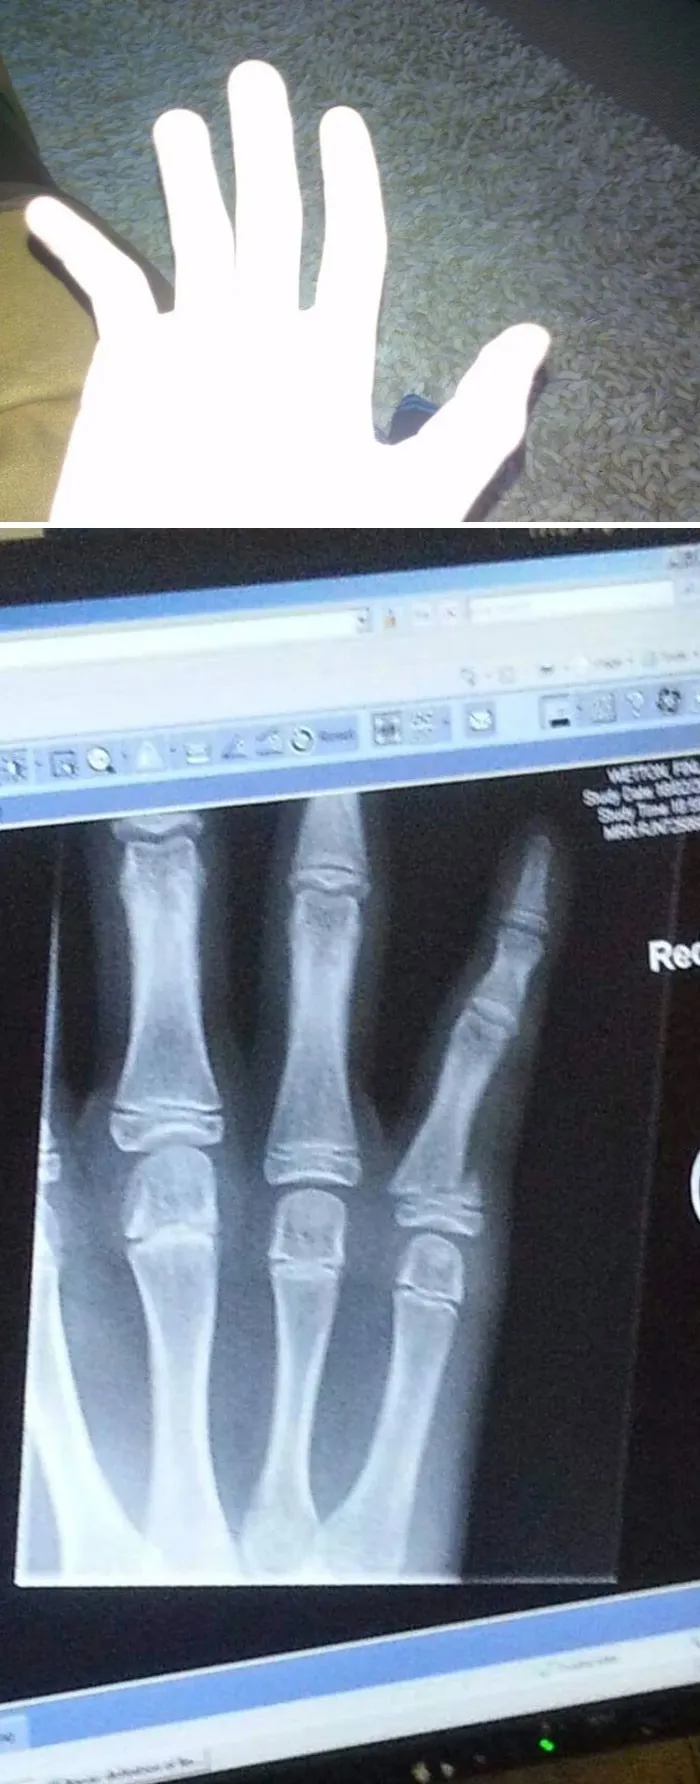

24. "Рентгеновский снимок моего перелома руки в детстве"

30. "Сломал палец в поисках чем бы перекусить"